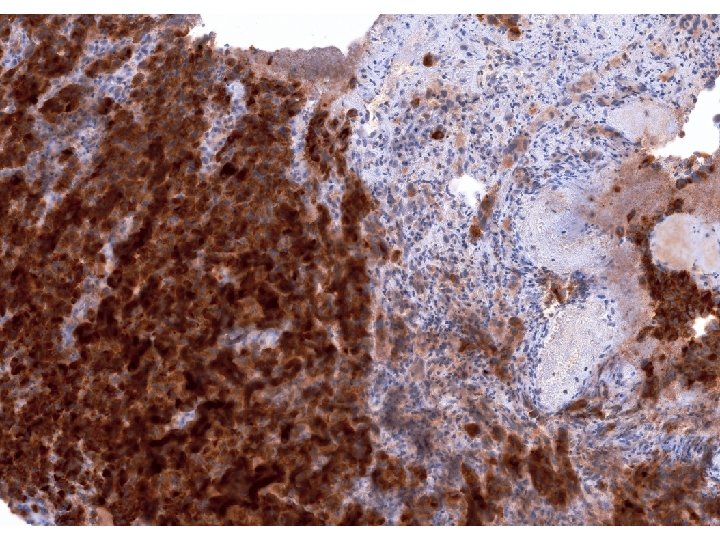

Imunohistologický nález nádorových buněk • K vyloučení nediferencovaného karcinomu vyšetřeny cytokeratiny, skupinovitě (AE 1/AE

Imunohistologický nález nádorových buněk • K vyloučení nediferencovaného karcinomu vyšetřeny cytokeratiny, skupinovitě (AE 1/AE 3), i jednotlivě, reakce nádorových buněk bylanegativní. • Také reakce na CD 117 na možný stromálmí nádor byla negativní. • Reakce na S 100 protein byla slabá, ale zřetelně pozitivní, silně pozitivní reakce byla na Melan A i na HMB 45.

Diagnostický závěr • Pozitivní reakce na Melan A a na S 100 protein svědčí

Diagnostický závěr • Pozitivní reakce na Melan A a na S 100 protein svědčí pro dg. maligního melanomu, negativní reakce na cytokeratiny a CD 117 vyloučily nediferencovaný karcinom a maligní stromální tumor. • Je tento nádor primární?